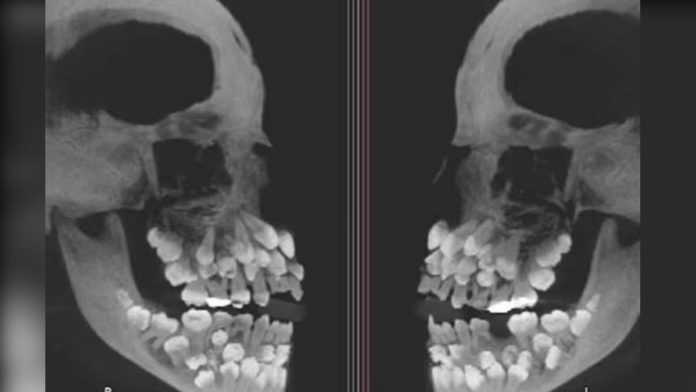

巴西一名11歲女孩因為想要拔牙而就診,沒想到牙醫在照X光時發現,女孩的口腔內竟然有多達81顆牙齒,罕見的病例震驚牙醫,這起罕見的病例被發布在醫學雜誌上後,引起討論。

據《朝鮮日報》報導,《VN Express》等外媒15日報導,這名來自巴西米納斯吉拉斯州的女孩,日前因為想拔除一顆上排乳牙而到醫院就診,但在拍攝X光後,醫師意外發現她口中竟藏有18顆乳牙、32顆恆牙,以及31顆多生牙,總數多達81顆。

一般成人的正常牙齒數量為32顆,超過正常數量額外長出的牙齒被稱為「多生牙」,通常多生牙是1至2顆,像該名巴西女童如此多的多生牙相當罕見。多生牙通常潛藏在牙齦內,可能阻礙正常牙齒或造成牙齒排列混亂,甚至引發囊腫等其他問題。

該病例由巴西胡伊斯迪福拉聯邦大學牙科醫院研究團隊發表,並刊登在美國《牙齒矯正與口腔顎面外科學會雜誌》,研究團隊透過精密影像檢查確認牙齒的確切位置,同時進行基因檢測,以判斷是否與遺傳疾病有關。

後續染色體檢查發現,巴西女童擁有一種罕見的遺傳變異,但研究人員表示,該變異與多生牙的直接關聯性尚無法確認。有些多生牙深埋於牙齦內或外型與正常牙齒相似,若貿然拔除可能導致顎骨受損,為降低風險,研究團隊已召集牙齒矯正科、口腔顎面外科、牙周病科與假牙科等多科醫師,共同擬定長期的治療計畫,盡可能保護該名女孩的口腔健康與未來牙齒排列。